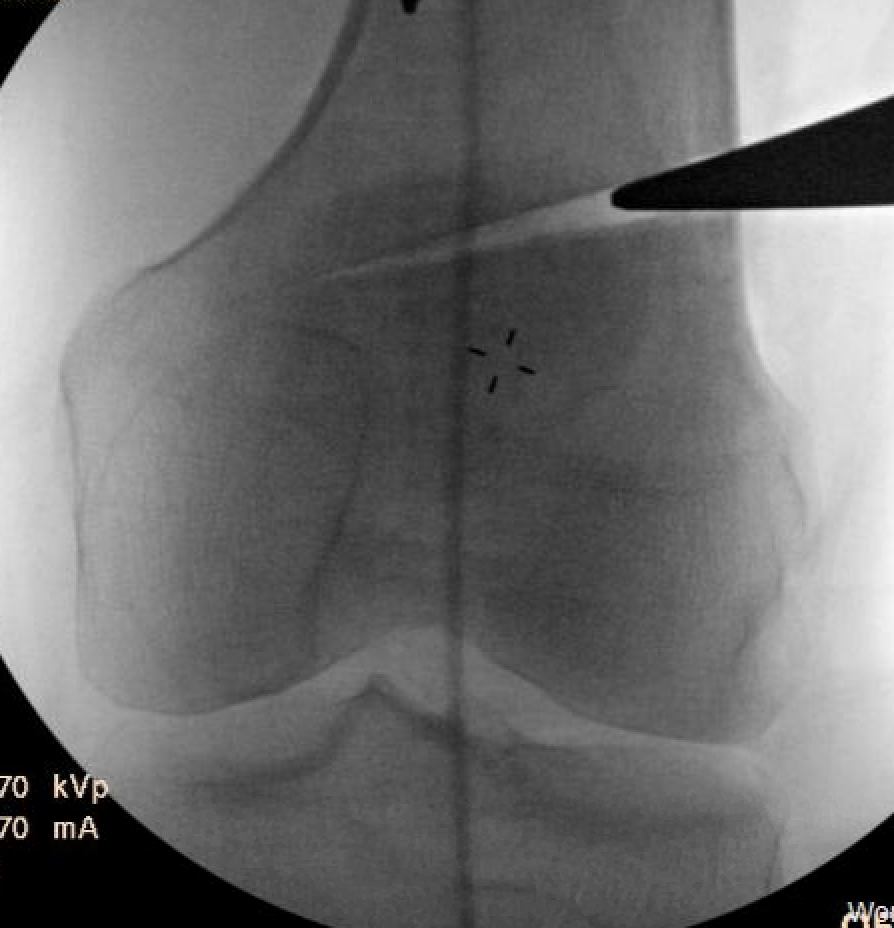

Osteotomy

- insert guide wires

- proximal lateral to distal medial

- proximal 1 - 2 cm above flare of lateral condyle

- aim towards adductor tubercle

- risk of medial hinge fracture reduced if osteotomy at or distal to adductor tubercle

- ensure these are perpendicular to the femoral shaft in the sagittal plane

- above patellofemoral joint and posterior condyles

- stop osteotomy 1 cm short of medial cortex